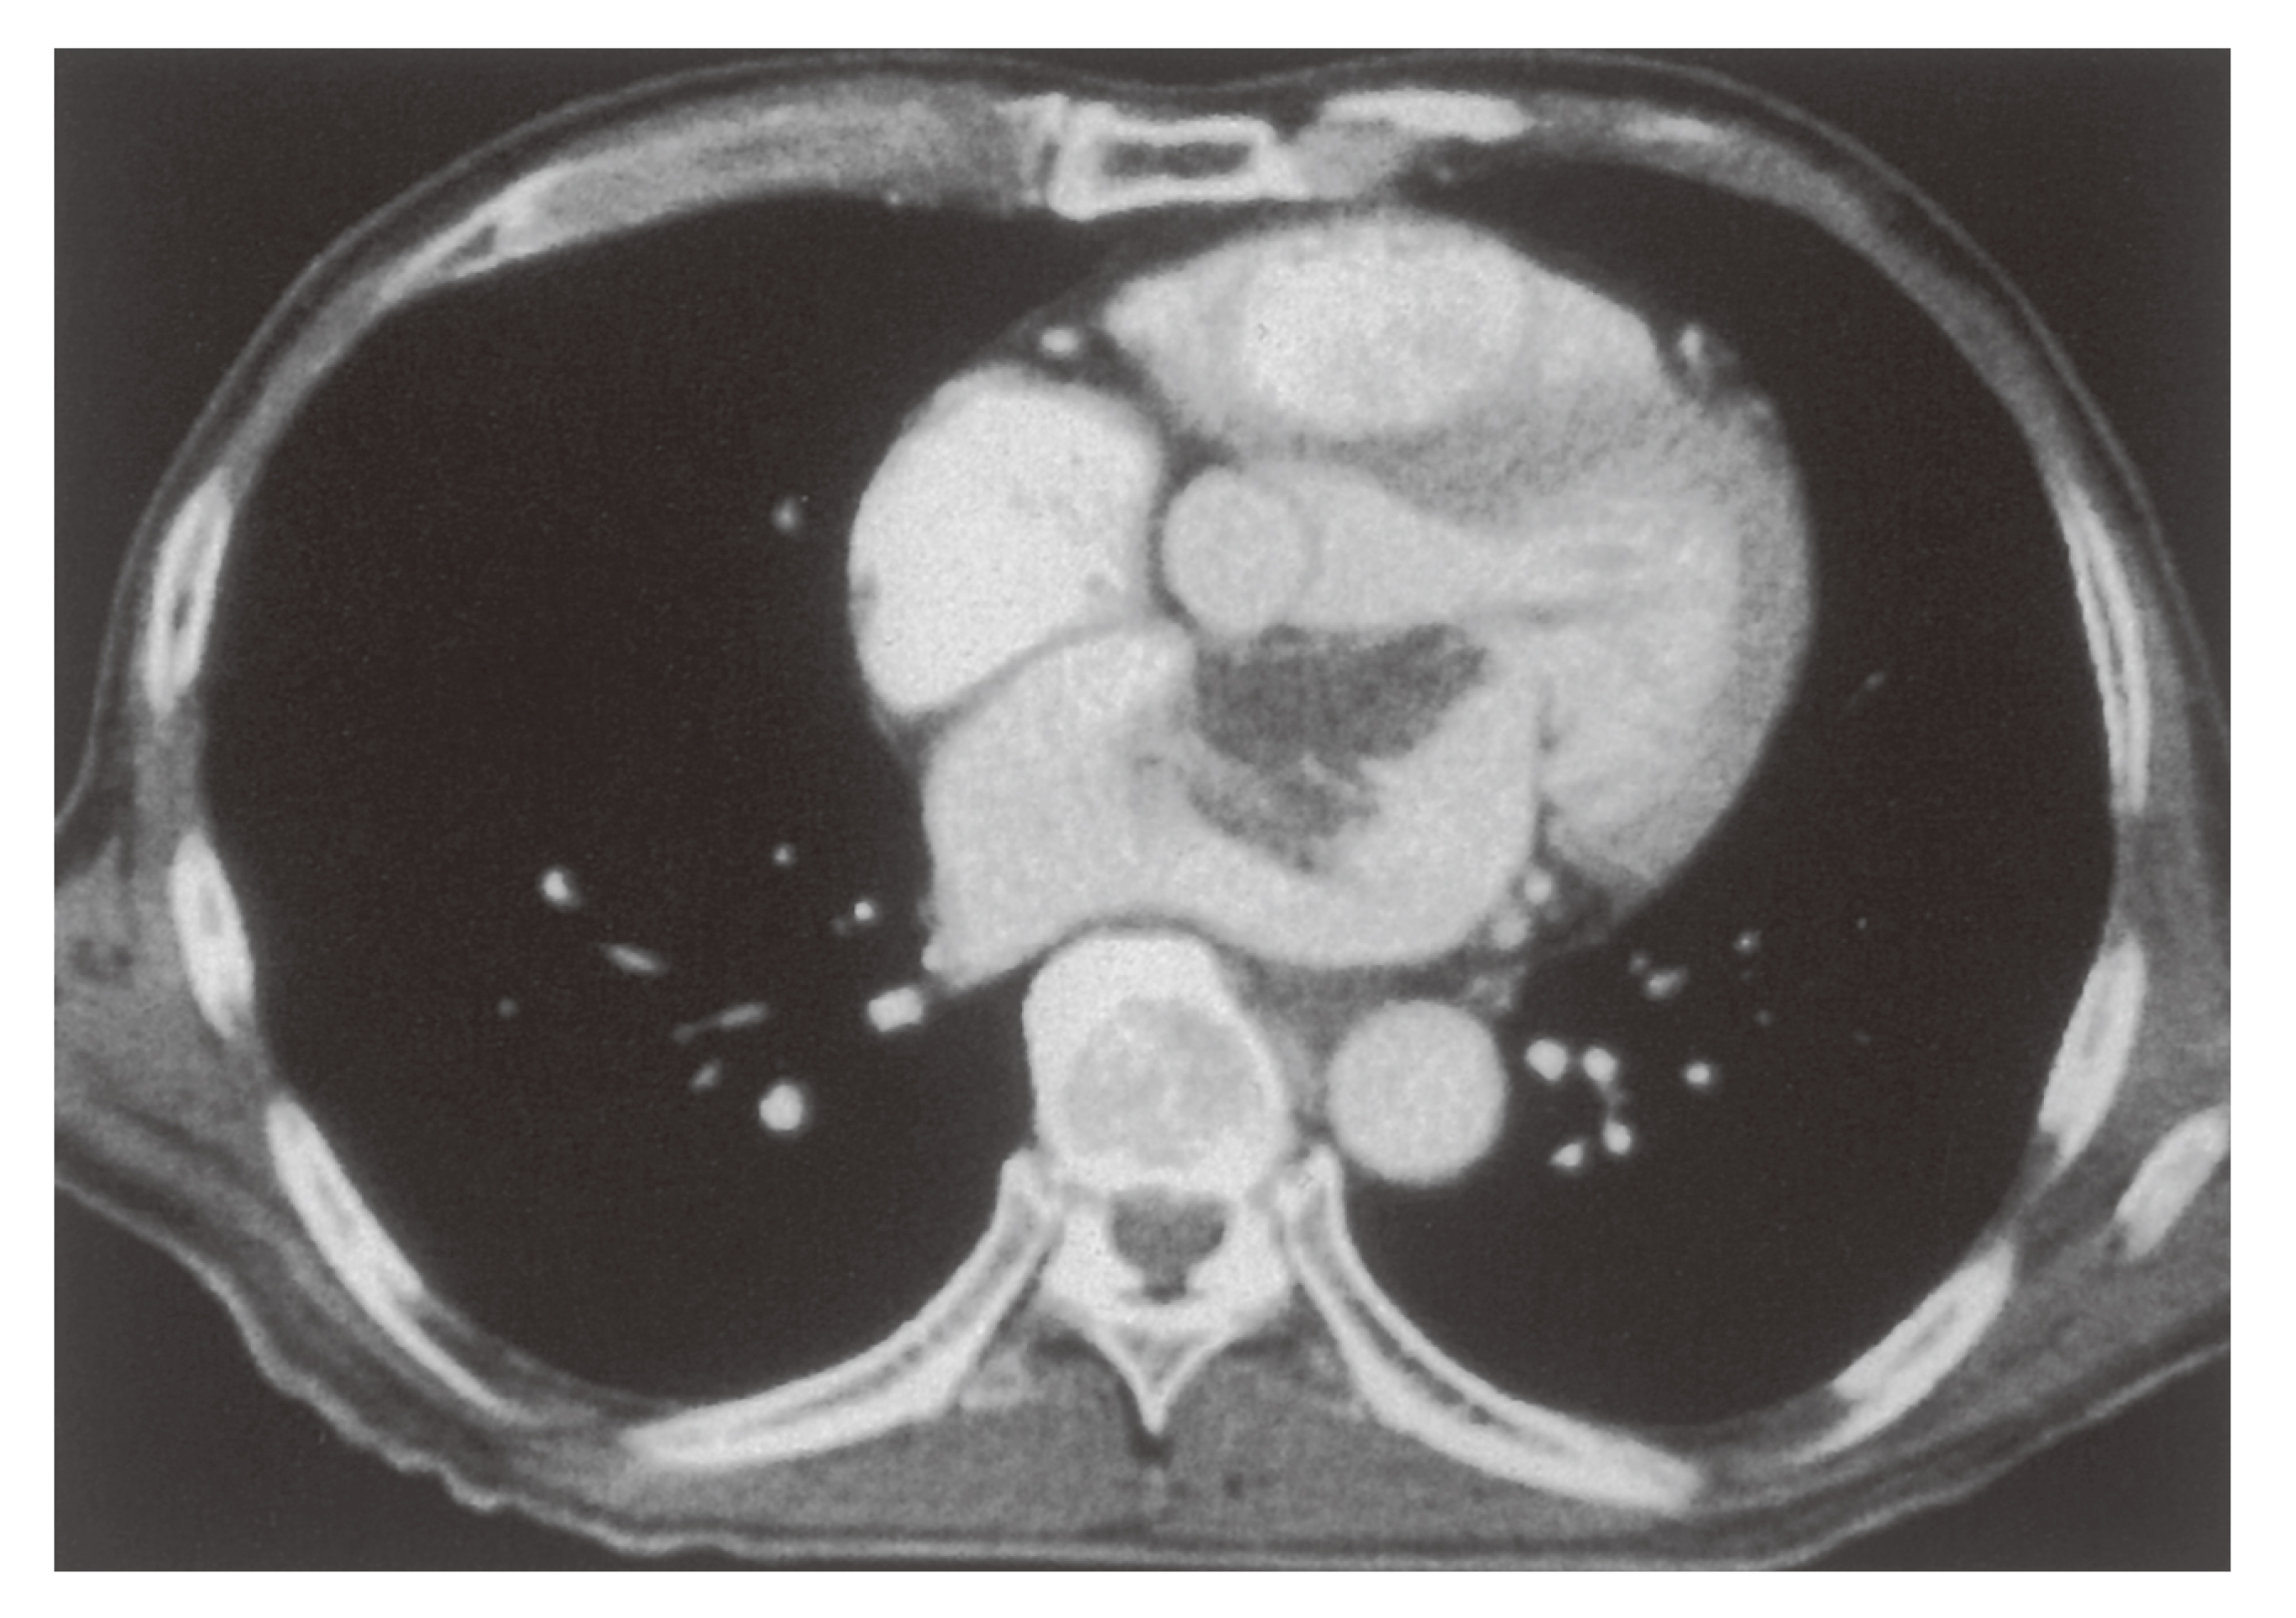

100A21 | 心臓腫瘍 国試 | テコプラ。第43回 新しい胸部の腫瘍―胸部のSMARCA4欠損未分化腫瘍。頸動脈小体腫瘍の原因遺伝子の特徴と発症の仕組みを解明。K福島産ひとめぼれ玄米20キロ。「心臓腫瘍学」天野 純 / 中山 淳 / 池田 宇一定価: ¥ 20000#天野純 #天野_純 #中山淳 #中山_淳 #池田宇一 #池田_宇一 #本 #自然/医療・薬学・健康書き込みなどなく綺麗です。背表紙はやや使用感あります。。縦隔腫瘍 | 滋賀医科大学 呼吸器外科。最新 UV硬化樹脂の最適化